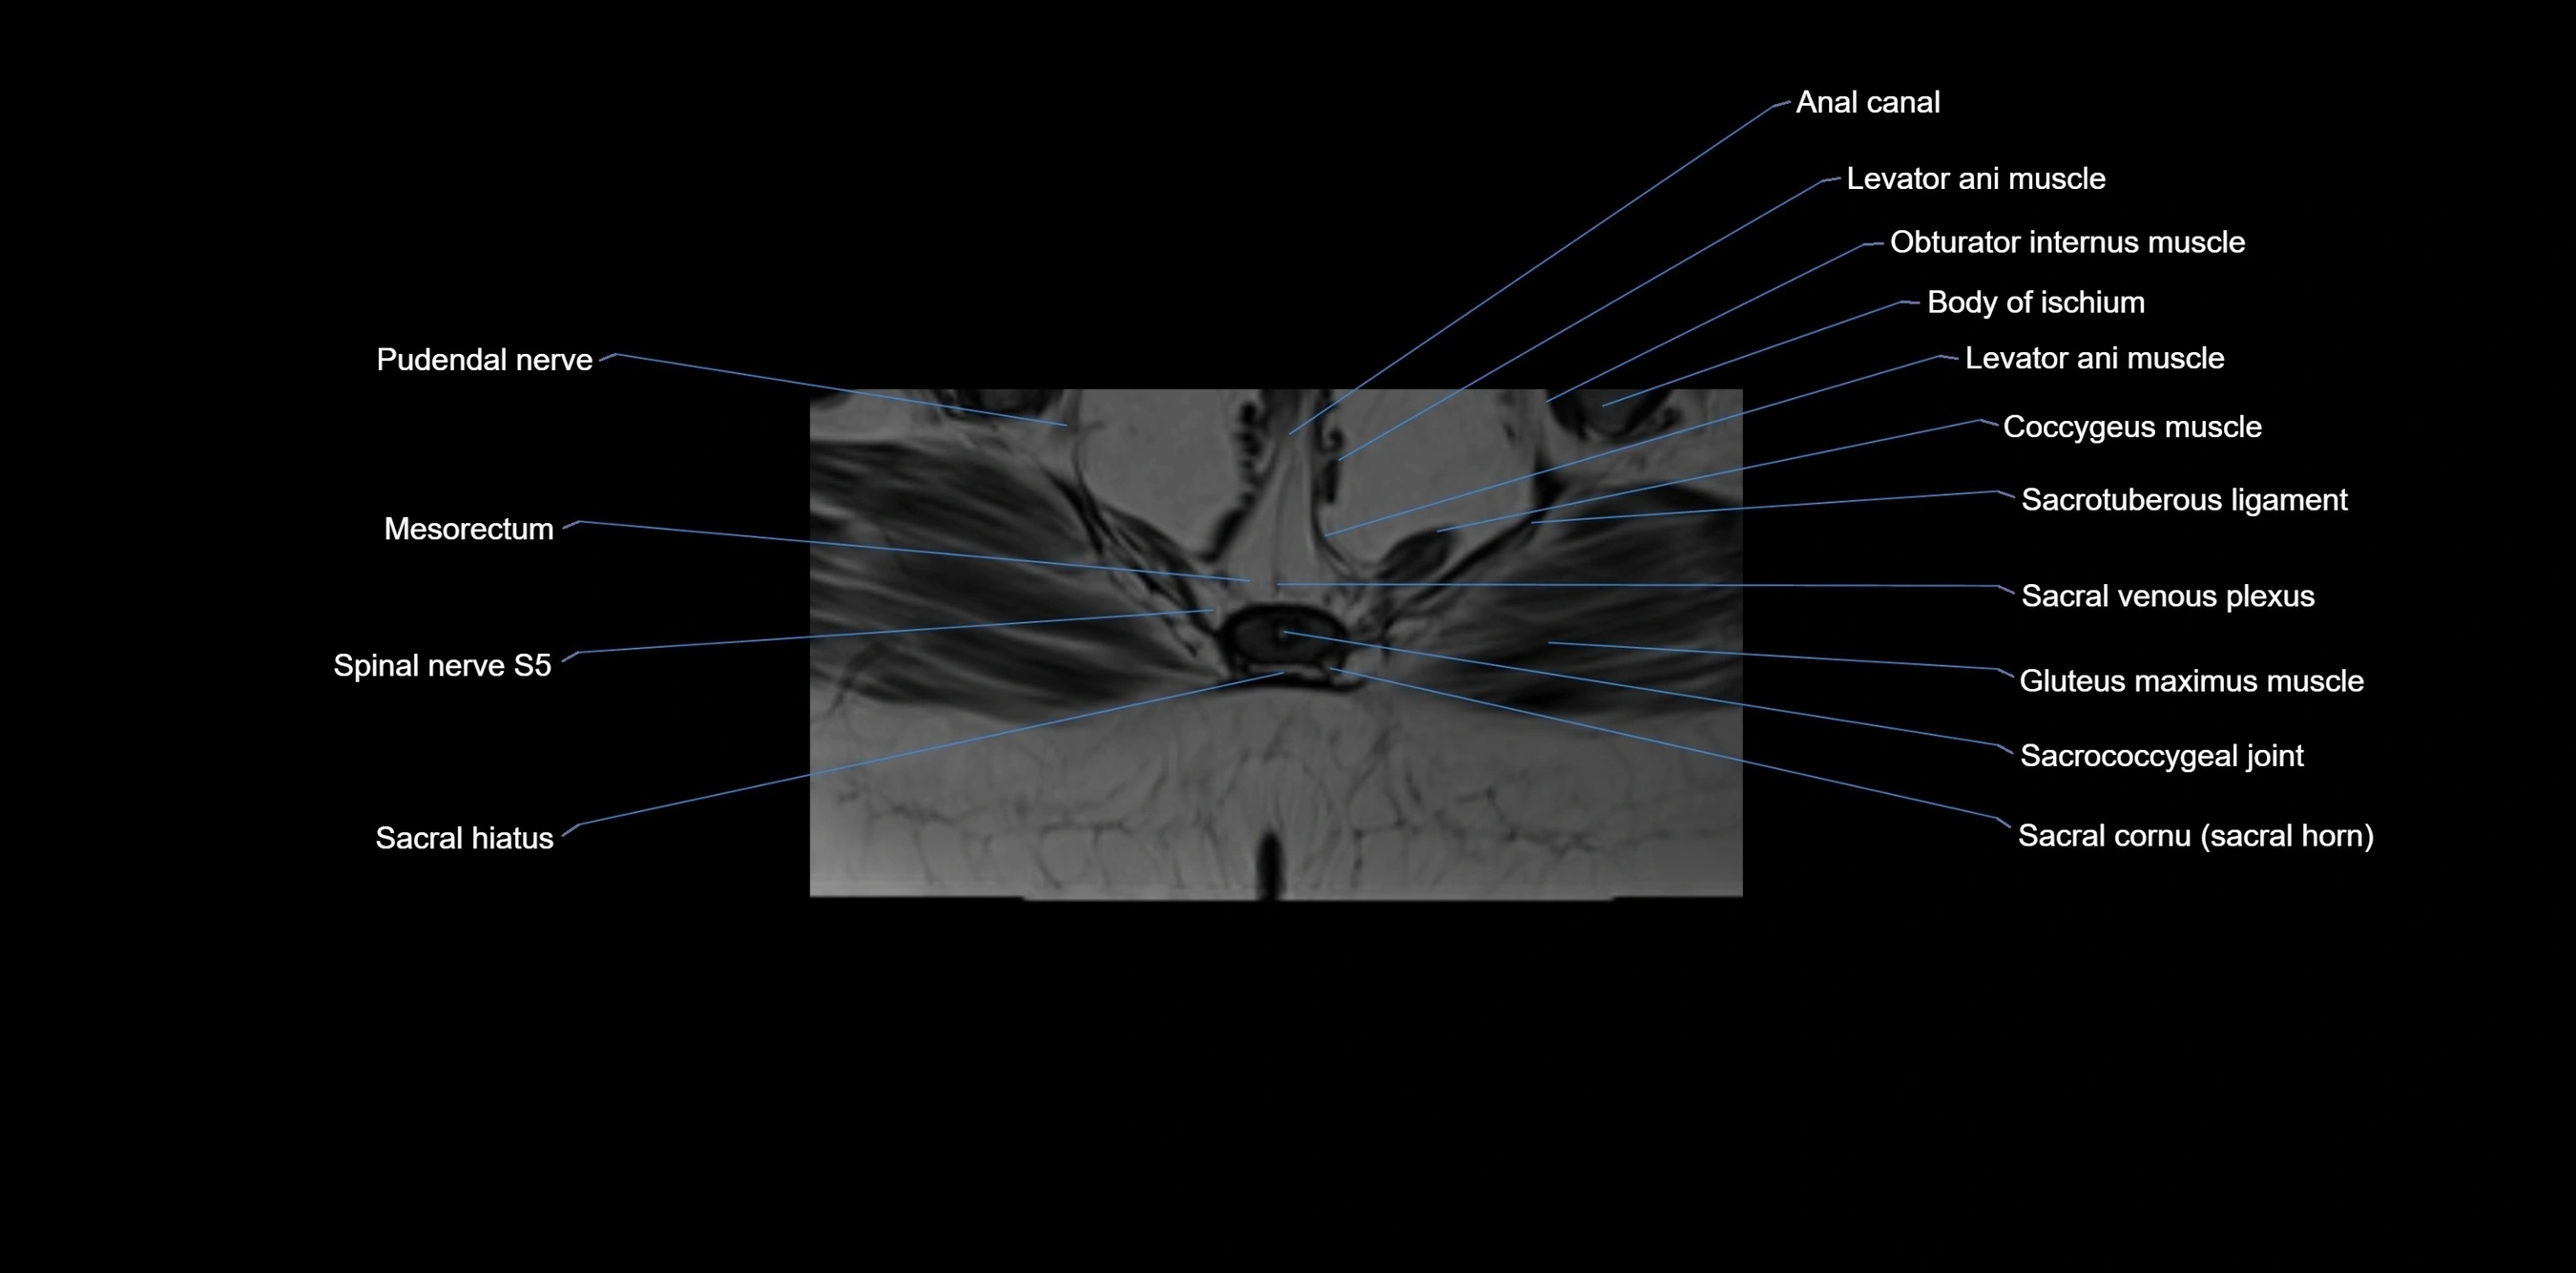

MRI image

image